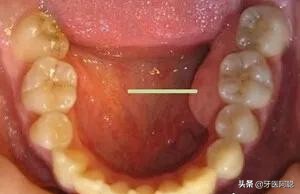

临床上,我们常常遇到患者说“牙龈上鼓了个包,硬硬的”,或镶牙的老人说“牙床压着疼”,通常可能是出现了牙槽骨骨质增生。

口腔内牙槽骨的骨质增生是指牙龈区域的牙槽骨出现骨质增生性突起,在临床上比较常见。

骨质增生的形式多种多样,因所在部位不同而有其各自的特点,在口腔中多表现多圆锥状突起或小骨刺,一般没有明显的临床症状,有时候伴有轻微的疼痛,可以通过X光摄片清晰地辨认骨质增生的部位和增生的程度。